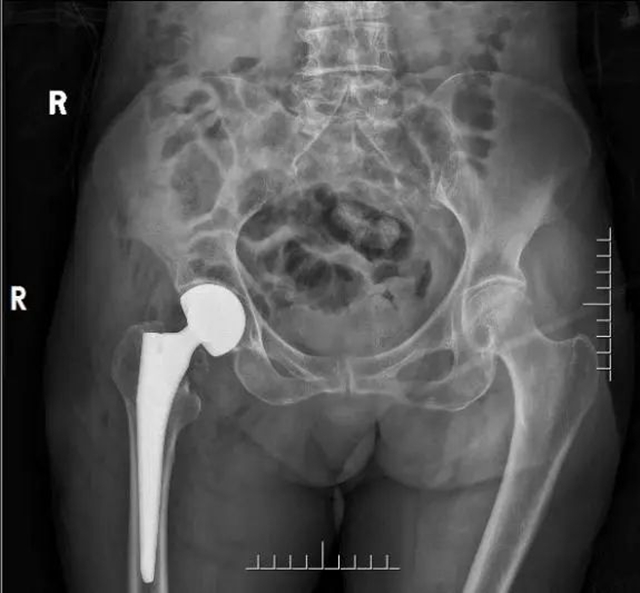

张婆婆术后X线

2022年5月4日,五一节假期的最后一天,经由神经内科、心血管内科、心身医学科、康复医学科会诊评估后,在骨与关节外科 、麻醉科、手术室的通力合作下,由李忠教授、尹一然副教授、鲜海医师共同为张婆婆实施了全麻下右髋关节半髋置换术。术后张婆婆安全返回病房,第二天便开始下地活动。